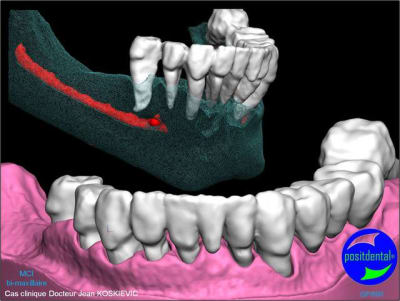

Extractions MCI en 1 chirurgie

gestion des artéfacts en présence de couronnes

chirurgie à venir

3D maxillaire inférieur et photo